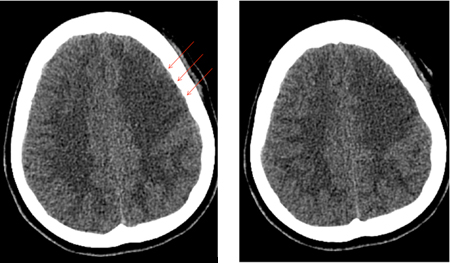

Subarachnoid hemorrhage

Left frontal infarct (arrows) in a patient with subarachnoid hemorrhage-related vasospasm

Courtesy of Dr Salah Keyrouz; used with permission